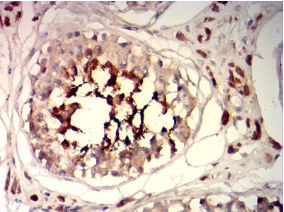

IHC    1/200-1/1000